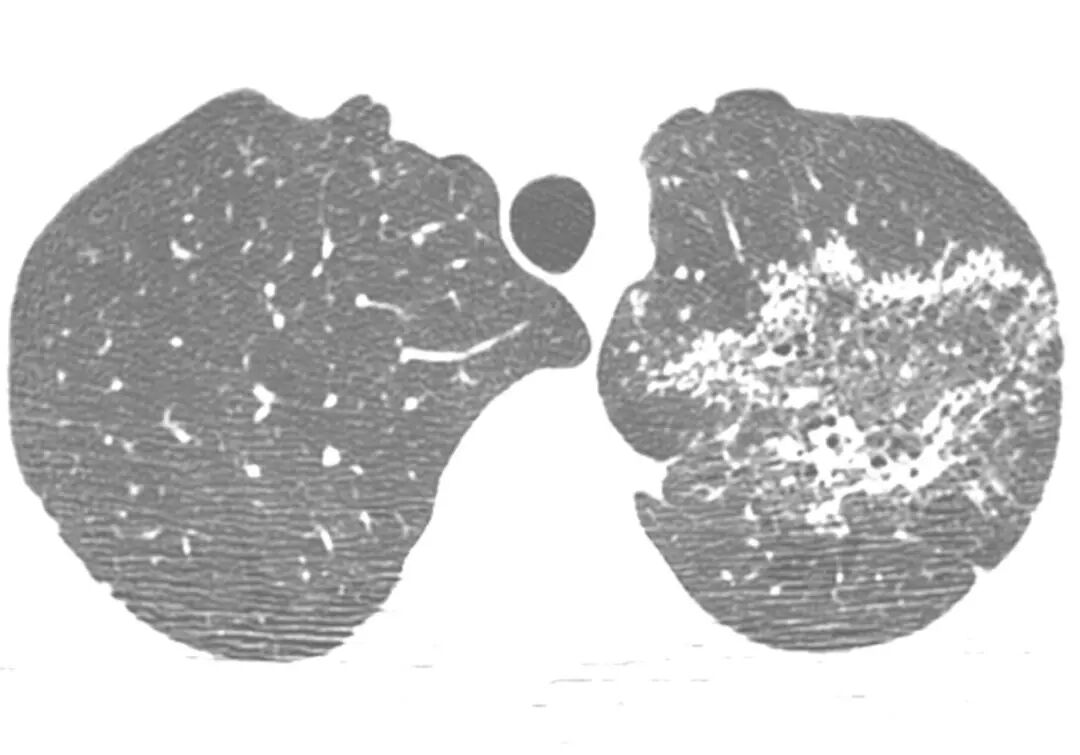

44岁的中年女性,既往健康,无症状,因新冠筛查而发现肺部阴影。肺部CT主要为双肺多发结节团块影,增强扫描纵隔窗显示左上肺前段的大片实变内有多发低密度影。当时大家讨论持各种意见的都有,包括转移瘤、真菌、结核或其他分枝杆菌,还有奴卡菌等等。

面对如此不典型的影像,只能继续往前工作。很快做了支气管镜,左上肺灌洗及肺活检均找到抗酸菌,灌洗液分枝杆菌培养Mtb(+)。所以有一句老调重提的话,临床上千万不要轻易排除结核,它可以模拟各种疾病。但是另一方面,深入理解结核病的病理机制,有助于认识一些反常临床表现的本质,而通过有目的地阅读肺部CT,仍可能在一些不典型的病例中发现提示结核的蛛丝马迹,为诊断提供线索。